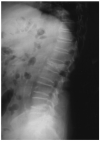

Vascular Calcification (VC), low bone mass and fragility fractures are frequently observed in ageing subjects. Although this clinical observation could be the mere coincidence of frequent age-dependent disorders, clinical and experimental data suggest that VC and bone loss could share pathophysiological mechanisms. Indeed, VC is an active process of calcium and phosphate precipitation that involves the transition of the vascular smooth muscle cells (VSMCs) into osteoblast-like cells. Among the molecules involved in this process, parathyroid hormone (PTH) plays a key role acting through several mechanisms which includes the regulation of the RANK/RANKL/OPG system and the Wnt/ß-catenin pathway, the main pathways for bone resorption and bone formation, respectively. Furthermore, some microRNAs have been implicated as common regulators of bone metabolism, VC, left ventricle hypertrophy and myocardial fibrosis. Elucidating the common mechanisms between ageing; VC and bone loss could help to better understand the potential effects of osteoporosis drugs on the CV system.